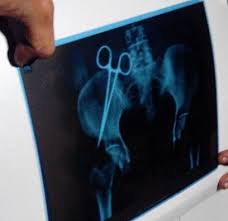

മംഗലാപുരം: നാലുവര്ഷമായി ഒരു സ്ത്രീയെ അലട്ടിയ പനിയുടെയും നീര്ക്കെട്ടിന്റെയും കാരണം കണ്ടെത്തി. ഉള്ളിൽ അകപ്പെട്ട ഒരു കത്രികയായിരുന്നു കാരണം. ഉള്ളാള് കൊടേക്കാര് ബീരിക്കടുത്ത മദൂര് സ്വദേശിനി ഹഫ്സയാണ് നാല് വർഷമായി വേദന തിന്നു ജീവിച്ചത്.

2010 ഫിബ്രവരി 22-ന് മംഗലാപുരത്തെ ഒരു നഴ്സിങ് ഹോമിൽ വെച്ച് ഗര്ഭപാത്രം നീക്കാനായി ശസ്ത്രക്രിയ നടത്തിയ ശേഷമാണ് ഇവർക്ക് തുടരെ തുടരെ പനി, നീര്ക്കെട്ട്, വേദന തുടങ്ങിയ പ്രശ്നങ്ങൾ കണ്ടു തുടങ്ങിയത്. ഇതേ കുറിച്ച് അറിയിച്ചപ്പോൾ ഗര്ഭപാത്രം നീക്കിയാലുണ്ടാകുന്ന പ്രശ്നങ്ങളാണിവയെന്നാണ് ഹോസ്പിറ്റൽ അതികൃതർ അറിയിച്ചത്. എന്നാല് ശസ്ത്രക്രിയ കഴിഞ്ഞ് നാളുകൾ പലത് കഴിഞ്ഞിട്ടും അസ്വസ്ഥതകള് ഒട്ടും കുറയാതായപ്പോളാണ് മറ്റൊരു ഡോക്ടറെ കാണിച്ചത്. അദ്ദേഹം അരക്കെട്ടിന്റെ എക്സ്റേയെടുക്കാന് നിര്ദേശിച്ചു. അതിലാണ് ശരീരത്തിനുള്ളിലായി കത്രിക കണ്ടെത്തിയത്. ഇതു കണ്ട ഹഫ്സയുടെ വീട്ടുകാർ ശസ്ത്രക്രിയ നടത്തിയ ആസ്പത്രിയെ തന്നെ സമീപിച്ചപ്പോൾ അവർ ‘ശസ്ത്രക്രിയ ചെയ്ത് കത്രിക നീക്കിത്തരാമെന്നും അതിനുള്ള ചിലവൊന്നും വഹിക്കെണ്ടതില്ലെന്നും സംഭവം പുറത്തുപറയാതിരുന്നാൽ മാത്രം മതി’ എന്നും ആയിരുന്നു പറഞ്ഞത്. എന്നാല്, വീട്ടുകാര് വിവരം മാധ്യമപ്രവര്ത്തകരെയും പോലീസിനേയും ആരോഗ്യവകുപ്പ് ഉദ്ധ്യോഗസ്ഥരെ അറിയിക്കുകയുമാണ് ചെയ്തത്.

പ്രശ്നം പുറത്തായതോടെ ശസ്ത്രക്രിയ നടത്തിയത് ഗര്ഭപാത്രം സ്ഥിതിചെയ്യുന്ന ഇടുപ്പിന്റെ മധ്യഭാഗത്താണെന്നും എക്സ്റേയില് കത്രിക കണ്ടെത്തിയത് ഒരു വശത്തായാണെന്നുമാണ് ശസ്ത്രക്രിയചെയ്ത ഡോക്ടറുടെ വാദം. മാത്രമല്ല വീണ്ടും ശസ്ത്രക്രിയ നടത്തിയാല് മാത്രമേ സംഭവിച്ചതെന്താണെന്ന് അറിയാൻ കഴിയു എന്നും ഡോക്ടർ പറഞ്ഞു.